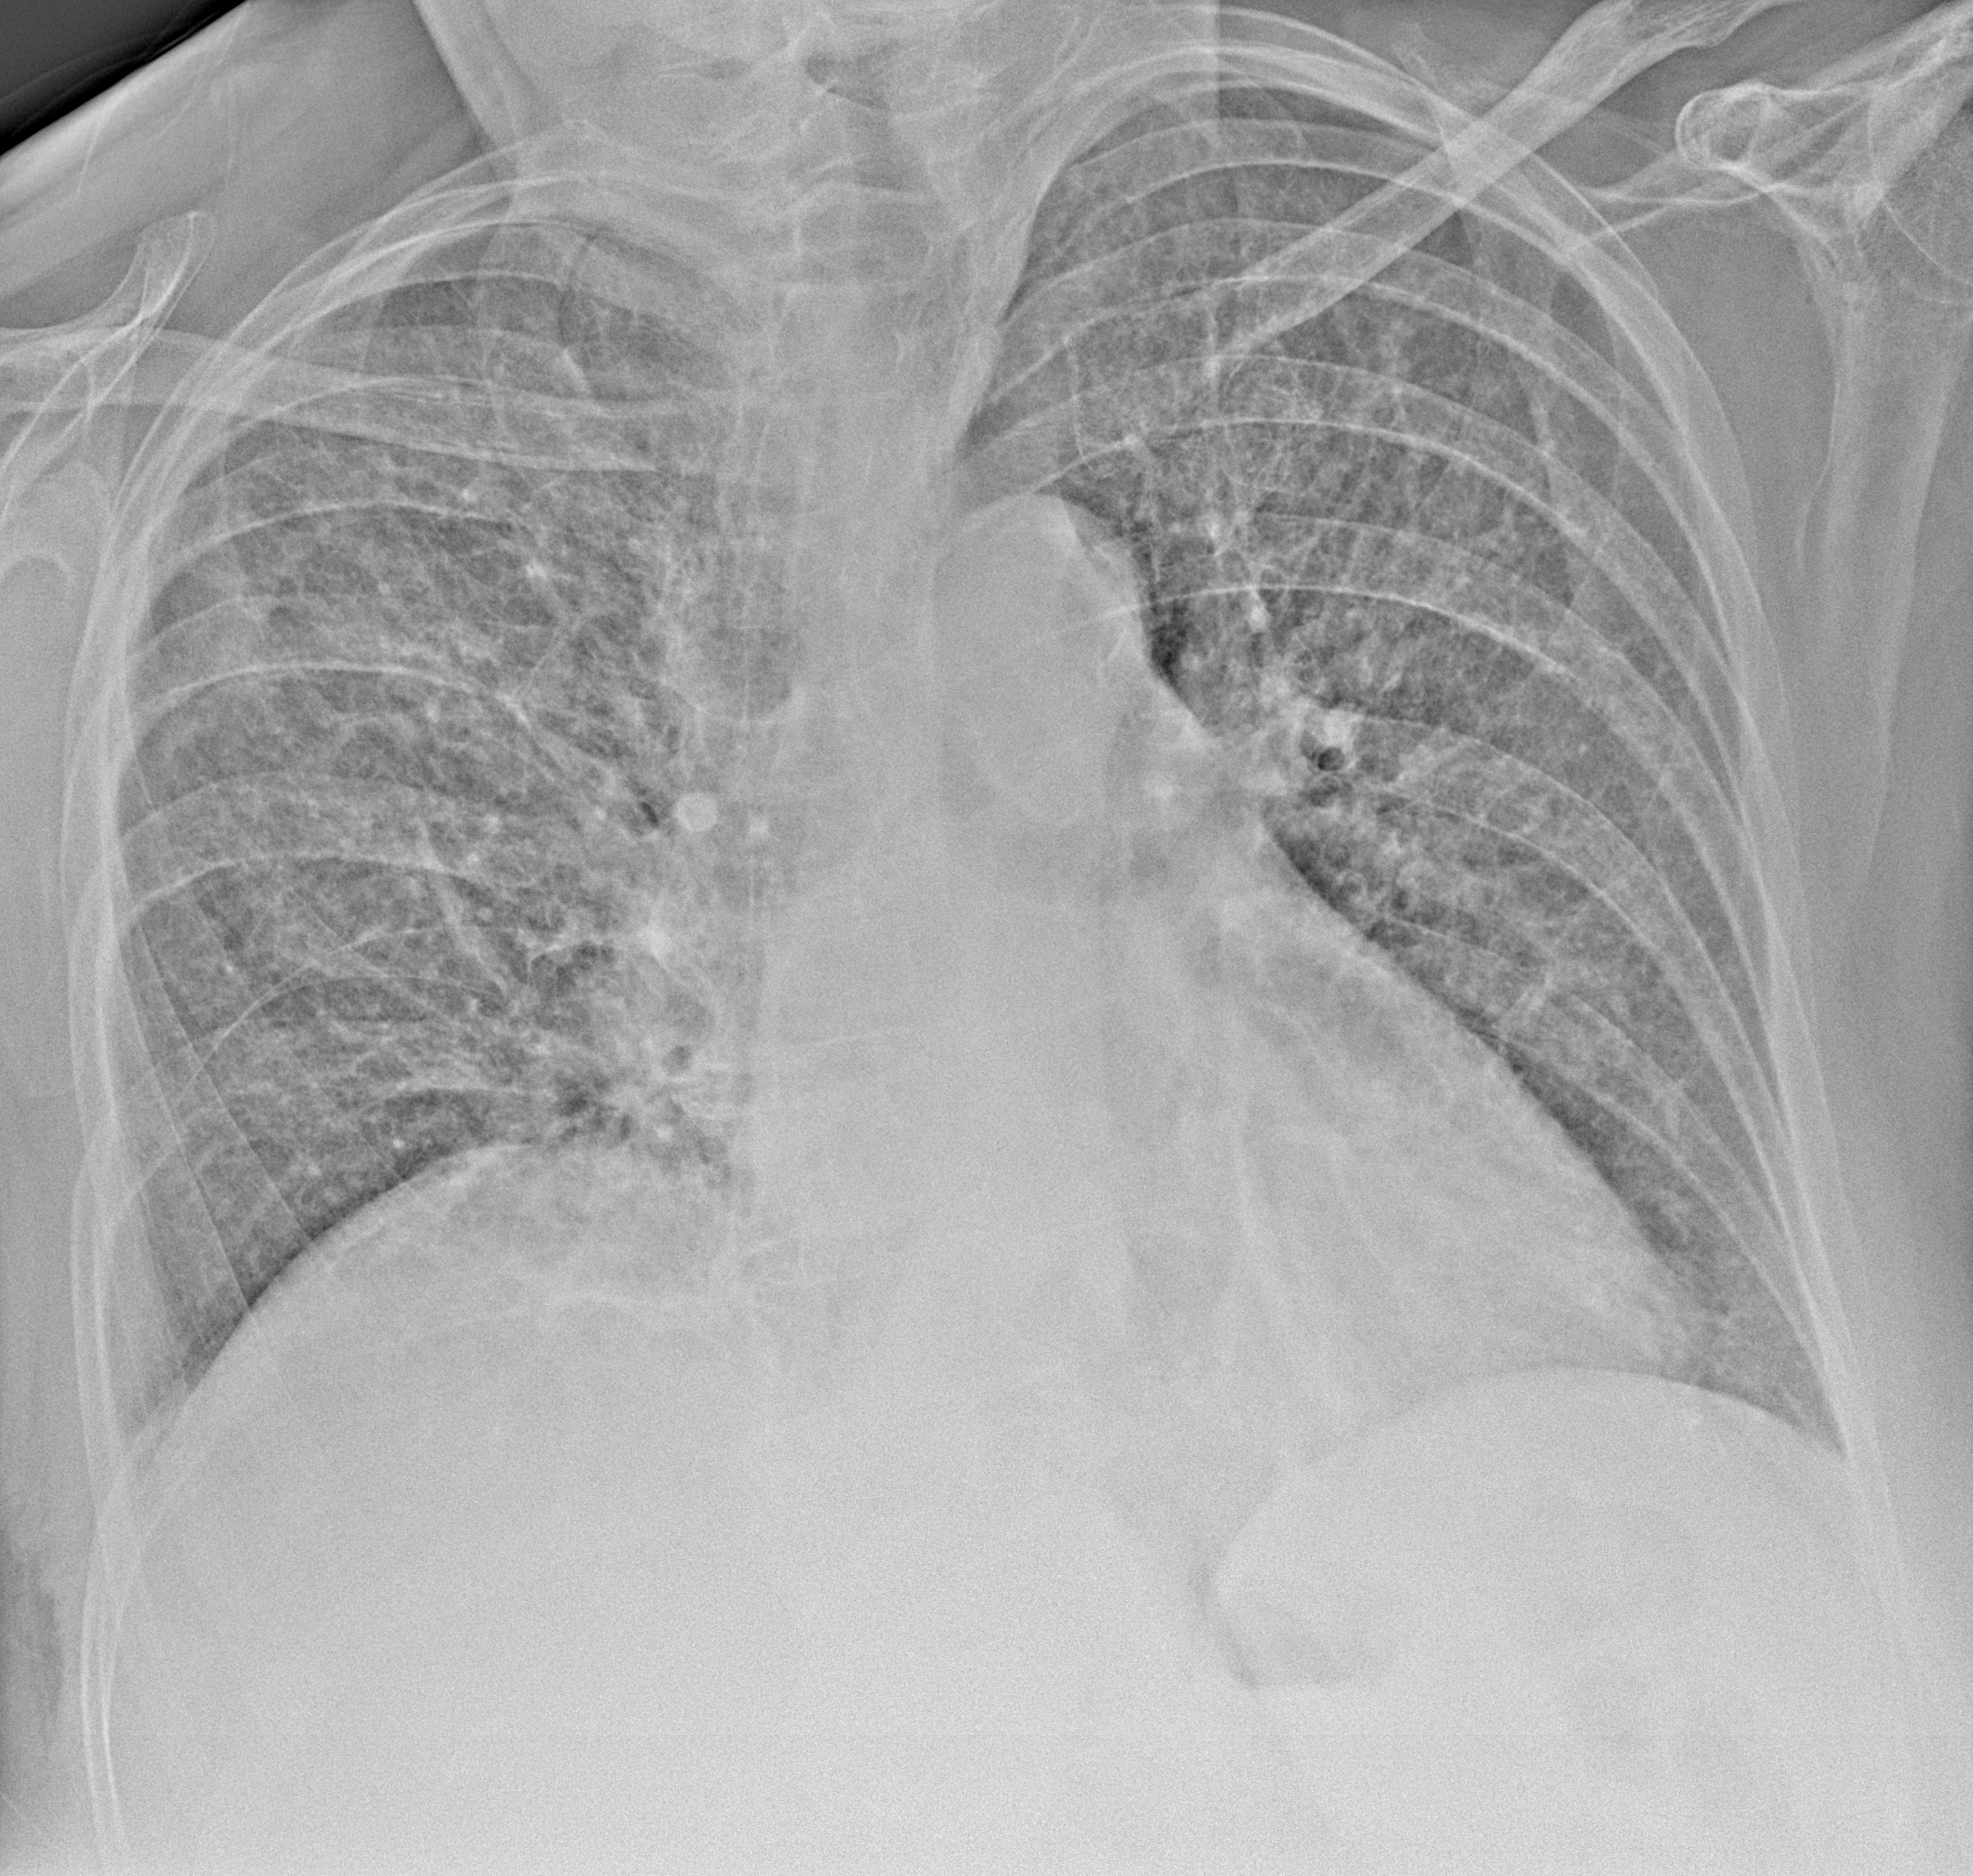

Пневмония

при переломе шейки бедра и пневмонии от компании МосРентген Центр - партнера Института имени Склифосовского